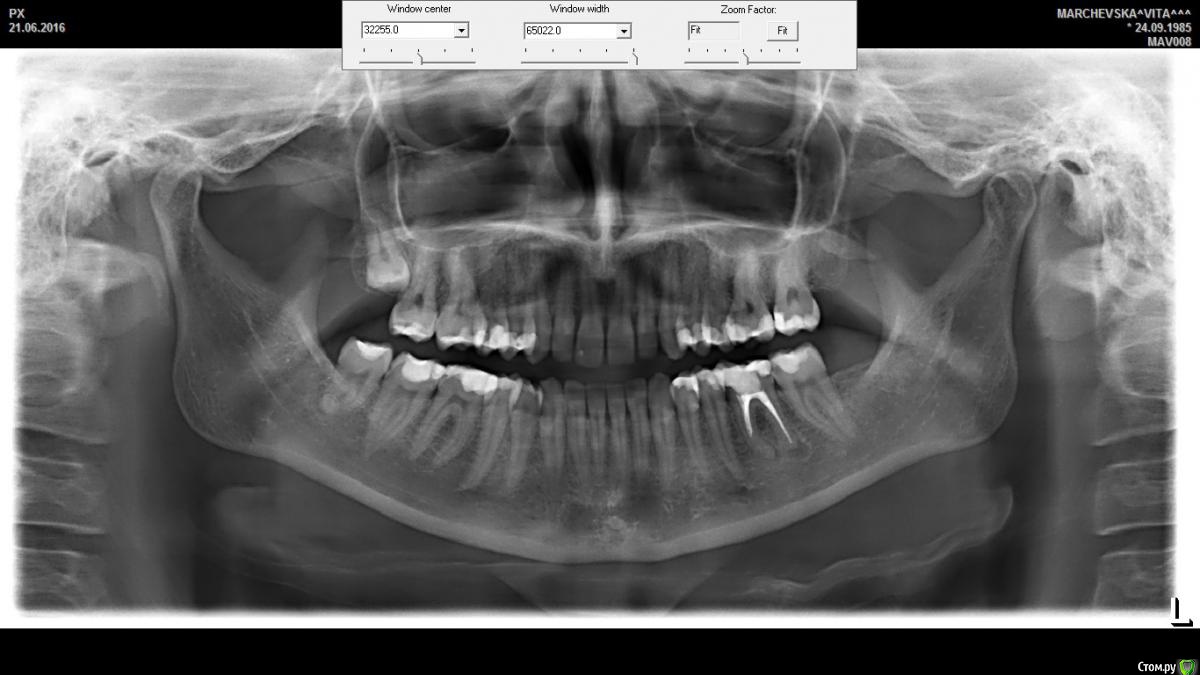

Vita85 Опубликовано 12 января, 2017 Поделиться Опубликовано 12 января, 2017 Добрый день, уважаемые! Помогите разобраться, так как окончательно утратила веру в лечащего врача. Ситуация такова. На консультации был обнаружен хронический периодонтит с образованием гранулемы на корне зуба.Врач объяснил, что необходимо перепломбировать каналы. 1 визит: вскрыли один из каналов, 2-ой врач не смог открыть. Отправил домой. Сказал в случае возникновения сильных болей пить антибиотик и обезбаливающие. Началось сильное воспаление. На 3-й день от боли уже стреляло в висках. Поехала в клинику. 2 визит: вскрыли временную пломбу, промыли каналы; было острое воспаление и много крови. Оставили открытым зуб. сказал, приходить через 4 дня. В этот же период мне становилось плохо от антибиотика. Поменяли на аугментин. 3 визит: снова промыли канал, второй канал так и не открыли. Сказали, что возможно каналы соединяются между собой и по-этому достаточно пролечить один. Назначили визит через неделю. 4 визит: запломбировали канал+ временная пломба.Врач сказал, что в случае болей опять пить антибиотик, а также сказал, что если через 3 месяца гранулема будет уменьшаться, то будем думать о коронке, а если нет - то, скорее всего, удаление. После пломбирования канала 3 дня не могла жевать, потом постепенно боль уходила. По-этому, через неделю я обратилась к другому врачу для консультации. Врач сказал, что нужно проверить через месяц и если не будет улучшений, то нужно пытаться вскрыть другой канал. Если не получится его вскрыть, то тогда уже думать: что делать дальше. А если будут улучшения, то нужно немедленно поставить постоянную пломбу. Вот я и запуталась... Подскажите, пожалуйста, как правильно поступить в данной ситуации?! Достаточно ли пролечить один канал, чтобы вылечить зуб? Что делать, если врач не может распломбировать канал? P.S второе фото спустя 3 дня после пломбирования канал ( извините за качество) Огромное спасибо все, кто откликнется!!! Ссылка на комментарий

St. Опубликовано 12 января, 2017 Поделиться Опубликовано 12 января, 2017 Достаточно ли пролечить один канал, чтобы вылечить зуб? Нет, воспаление есть на обоих корнях, и там где не дошли до конца канала микробы осталось, соответственно воспаление там будет продолжаться.Ситуация осложняется тем, что корень этот достаточно изогнутый, и доктор в поисках канала создал прямолинейную дорожку, не найдя канал.Опять же, оставление зубов открытыми по современным взглядам не есть хорошо.. Вариантов у Вас несколько:1. Ничего не делать пока не болит, поставить условно постоянную пломбу.Из + сейчас ничего не надо решать, финансовых вложений минимумИз - зуб все равно со временем начнет беспокоить, и условия имплантации могут быть хуже2. Пробовать перелечить непройденный каналИз+ пытаться сохранить зуб максимально надолгоИз - негарантированно и непрогнозируемо, возможно что после перелечивания зуб все равно пойдет на удаление.3. Удалить и мостИз - удаление зуба, страдают соседние живые зубы4. Удалить и имплант.Из + максимально прогнозируемоИз - удаление зуба, определенные финансовые вложение. 2 Ссылка на комментарий

Vita85 Опубликовано 13 января, 2017 Автор Поделиться Опубликовано 13 января, 2017 Сохранить , 3 месяца наблюдать и контроль снимок, в случаи обострения удалить. Если лечили в том же месяце 21.06.16 снимки свежие в студию.. Спасибо за ответ! Зуб начали лечить в конце ноября, пломбирование канала - 20 декабря. На следующей неделе (получается спустя месяц после плом канала) должна сделать снимок и дальше принять решение. Подскажите,пожалуйста, в данной ситуации возможен положительный исход и спасение зуба?! Хоть я и не врач, но вижу на снимке, что канал не запломбирован до конца... Можно ли оставлять все в таком состоянии? Мне врач говорит, что, возможно, каналы соеденены, хоть этого и не видно на снимке. И , если пролечен один канал, то второй может излечится благодаря моему организму (иммунитету). Это реально? Ссылка на комментарий

St. Опубликовано 13 января, 2017 Поделиться Опубликовано 13 января, 2017 Как я понимаю, если не прочистить второй канал, то исход лечения - однозначно уделение, только отстроченное по времени? Да, правильно. Как мне объяснил врач, что, возможно, каналы соединяются, хотя этого и не видно на снимке. И достаточно пролечить один, а дальше все зависит от того, как организм ( иммунитет) справиться с воспалением! Это реально? В теории словами описано все правильно, но это не про Ваш случай, увы.. У Вас в ближнем корне канал до верхушки не пролечен, поэтому о выздоровлении говорить нельзя. Максимум - может на какое-то время не беспокоить. И, что касается импланта, скажите сколько времени необходимо для установки импланта ( минимально короткий срок)? В зависимость от сложности удаления - или сразу или через 2-3 месяца.Если есть вопросы по имплантации - лучше спросите в хирургическом разделе, так будет максимально приближено к правде. Ссылка на комментарий